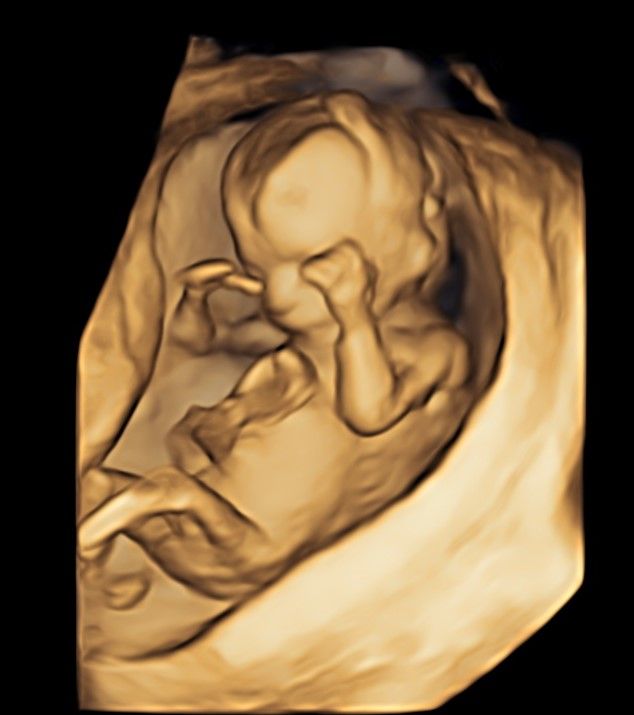

Foto e video